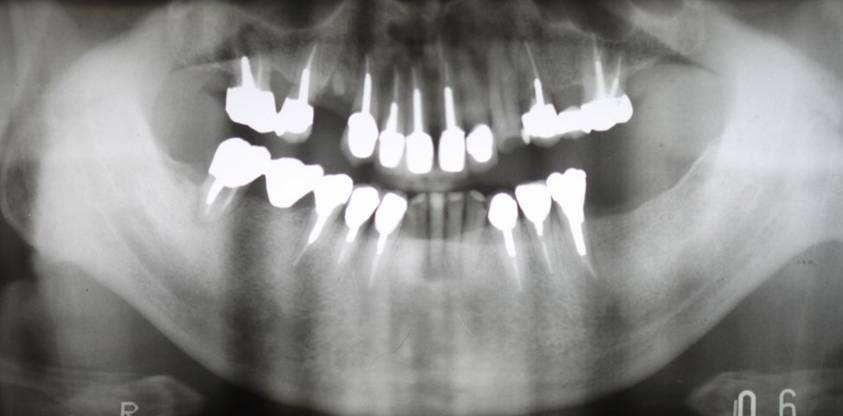

術前パノラマレントゲン写真。根の周りが黒くなり、骨がなくなっていることがわかります

術前。すべての歯が歯周病の末期状態でブリッジ全体がうごいて噛めないとの訴え。右上の犬歯が腫れていました

固定式のブリッジが入っていましたが歯周病で動いています

下顎前歯部には歯石の沈着がみられます